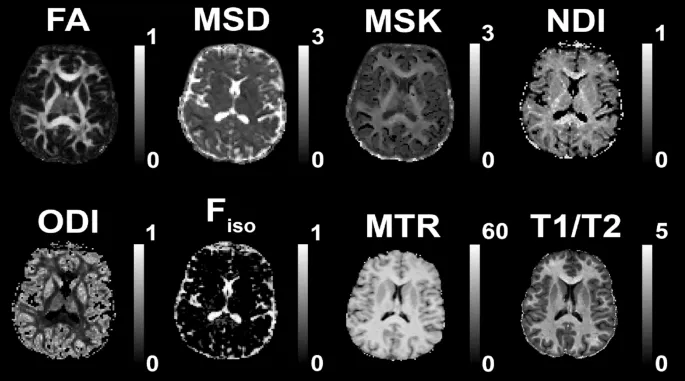

Магнитно-резонансная томография (МРТ) предлагает несколько методов для неинвазивной оценки состояния БВ:

- Диффузионно-взвешенная визуализация (DWI) — измеряет микроструктурные особенности, такие как плотность волокон.

- T1-взвешенная и T2-взвешенная МРТ — оценивают макроструктурные параметры, включая общий объем БВ и наличие гипертензивных очагов.

- Магнизационно-трансферная визуализация (MT) и отношение T1/T2 — используются как косвенные показатели содержания миелина.

Анализ 11 метрик БВ выявил четыре ключевых фактора, объясняющих 89% вариативности данных:

- Плотность волокон/миелинизация — коррелирует с фракционной анизотропией (FA) и индексом плотности нейритов (NDI).

- Свободная вода/повреждение тканей — связан с объемом свободной воды (Fiso) и гипертензивными очагами (WMHI).

- Сложность конфигурации волокон — определяется индексом дисперсии ориентации волокон (ODI).

- Микроструктурная сложность/объем — отражает общую организацию БВ.